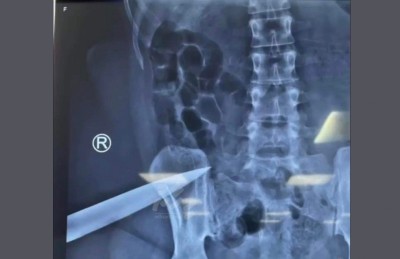

"މިހާރު" އަށް އެނގިފައިވާ ގޮތުގައި އަންހެން މީހާ ހޮސްޕިޓަލަށް ގެންދިޔައިރު ހެރިފައި އިން ވަޅީގެ މުއްގަނޑެއް ނެތެވެ. ހެރިފައި އިނީ ތިލަ އެވެ. އެހެންވެ ބެލެވޭ ގޮތުން، ގޭތެރެއިން ފެނުނު ތިލަ ނެތް ވަޅި އަކީ އެއީ އެވެ.

ފުލުހުން ކޯޓުގައި ބުނި ގޮތުގައި އަންހެން މީހާ ހޮސްޕިޓަލަށް ގެންގޮސް ބެލި އިރު ފައިގެ ފަލަމަސްގަނޑުގައި ދެ ޒަހަމެއް ހުއްޓެވެ. އަދި ފަލަމަސްގަނޑު ތެރޭ ވަޅިއެއްގެ ތިލަ އޮތްތަން އެކްސްރޭ އިން ފެނެ އެވެ. ފިރިހެން މީހާ އަމިއްލަ ބަނޑަށް ހެރީ ފުލުހުން ސީނަށް ދިޔައިރު ވެސް ފިރިހެން މިހާ އަތުގައި އޮތް ވަޅިން ކަމަށް ވެސް ފުލުހުން ބުނެފައިވެ އެވެ.